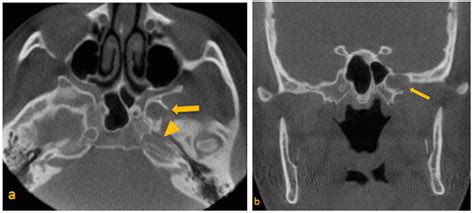

• Trauma and Fractures: Fractures of the Greater Sphenoid Wing can occur due to trauma, such as motor vehicle accidents or falls. These fractures can be complex and may require surgical intervention to restore the skull's integrity.

• Computed Tomography (CT): CT scans provide detailed images of the bony structures, making them ideal for evaluating fractures, tumors, and other abnormalities in the Greater Sphenoid Wing.

• Fractures: Fractures of the Greater Sphenoid Wing can occur due to trauma and may require surgical intervention to restore the skull's integrity.

Fractures Trauma Pain, swelling, neurological deficits Surgical repair, rehabilitation